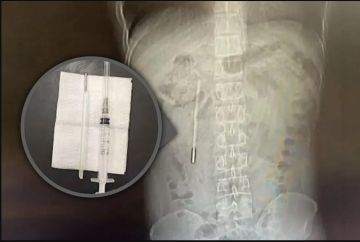

أُصيب رجل صيني يبلغ من العمر 32 عامًا، كان يعاني من آلام في المعدة، بصدمة بعد أن اكتشف أن سبب معاناته يعود إلى ميزان حرارة زئبقي ابتلعه قبل نحو 20 عامًا، ولا يزال عالقًا داخل جسده.

وكان الرجل، ويدعى وانغ، من مدينة ونتشو في مقاطعة تشجيانغ جنوب شرق الصين، قد خضع للعلاج في فرع لونغغانغ التابع للمستشفى الأول المرتبط بجامعة ونتشو الطبية. وكشف الفحص الطبي عن وجود جسم غريب في الاثني عشر، يُشتبه بشدة في أنه ميزان حرارة زئبقي، حيث كان الطرف المعدني يضغط مباشرة على جدار الأمعاء، ما شكّل خطرًا كبيرًا لاحتمال حدوث ثقب أو نزيف داخلي حاد.

وأفادت صحيفة «ساوث تشاينا مورنينغ بوست» أن العملية الجراحية كانت بالغة الدقة، نظرًا لبقاء الميزان داخل الجسم لفترة طويلة، وقربه من القنوات الصفراوية، ما زاد من خطورة التدخل الجراحي واحتمال إصابة جدار الأمعاء. ومع ذلك، تمكن الجراحون من إزالة الجسم الغريب خلال 20 دقيقة فقط، حيث ظهر «الترمومتر» سليمًا إلى حد كبير، رغم بهتان علامات القياس عليه، بحسب الصحيفة.